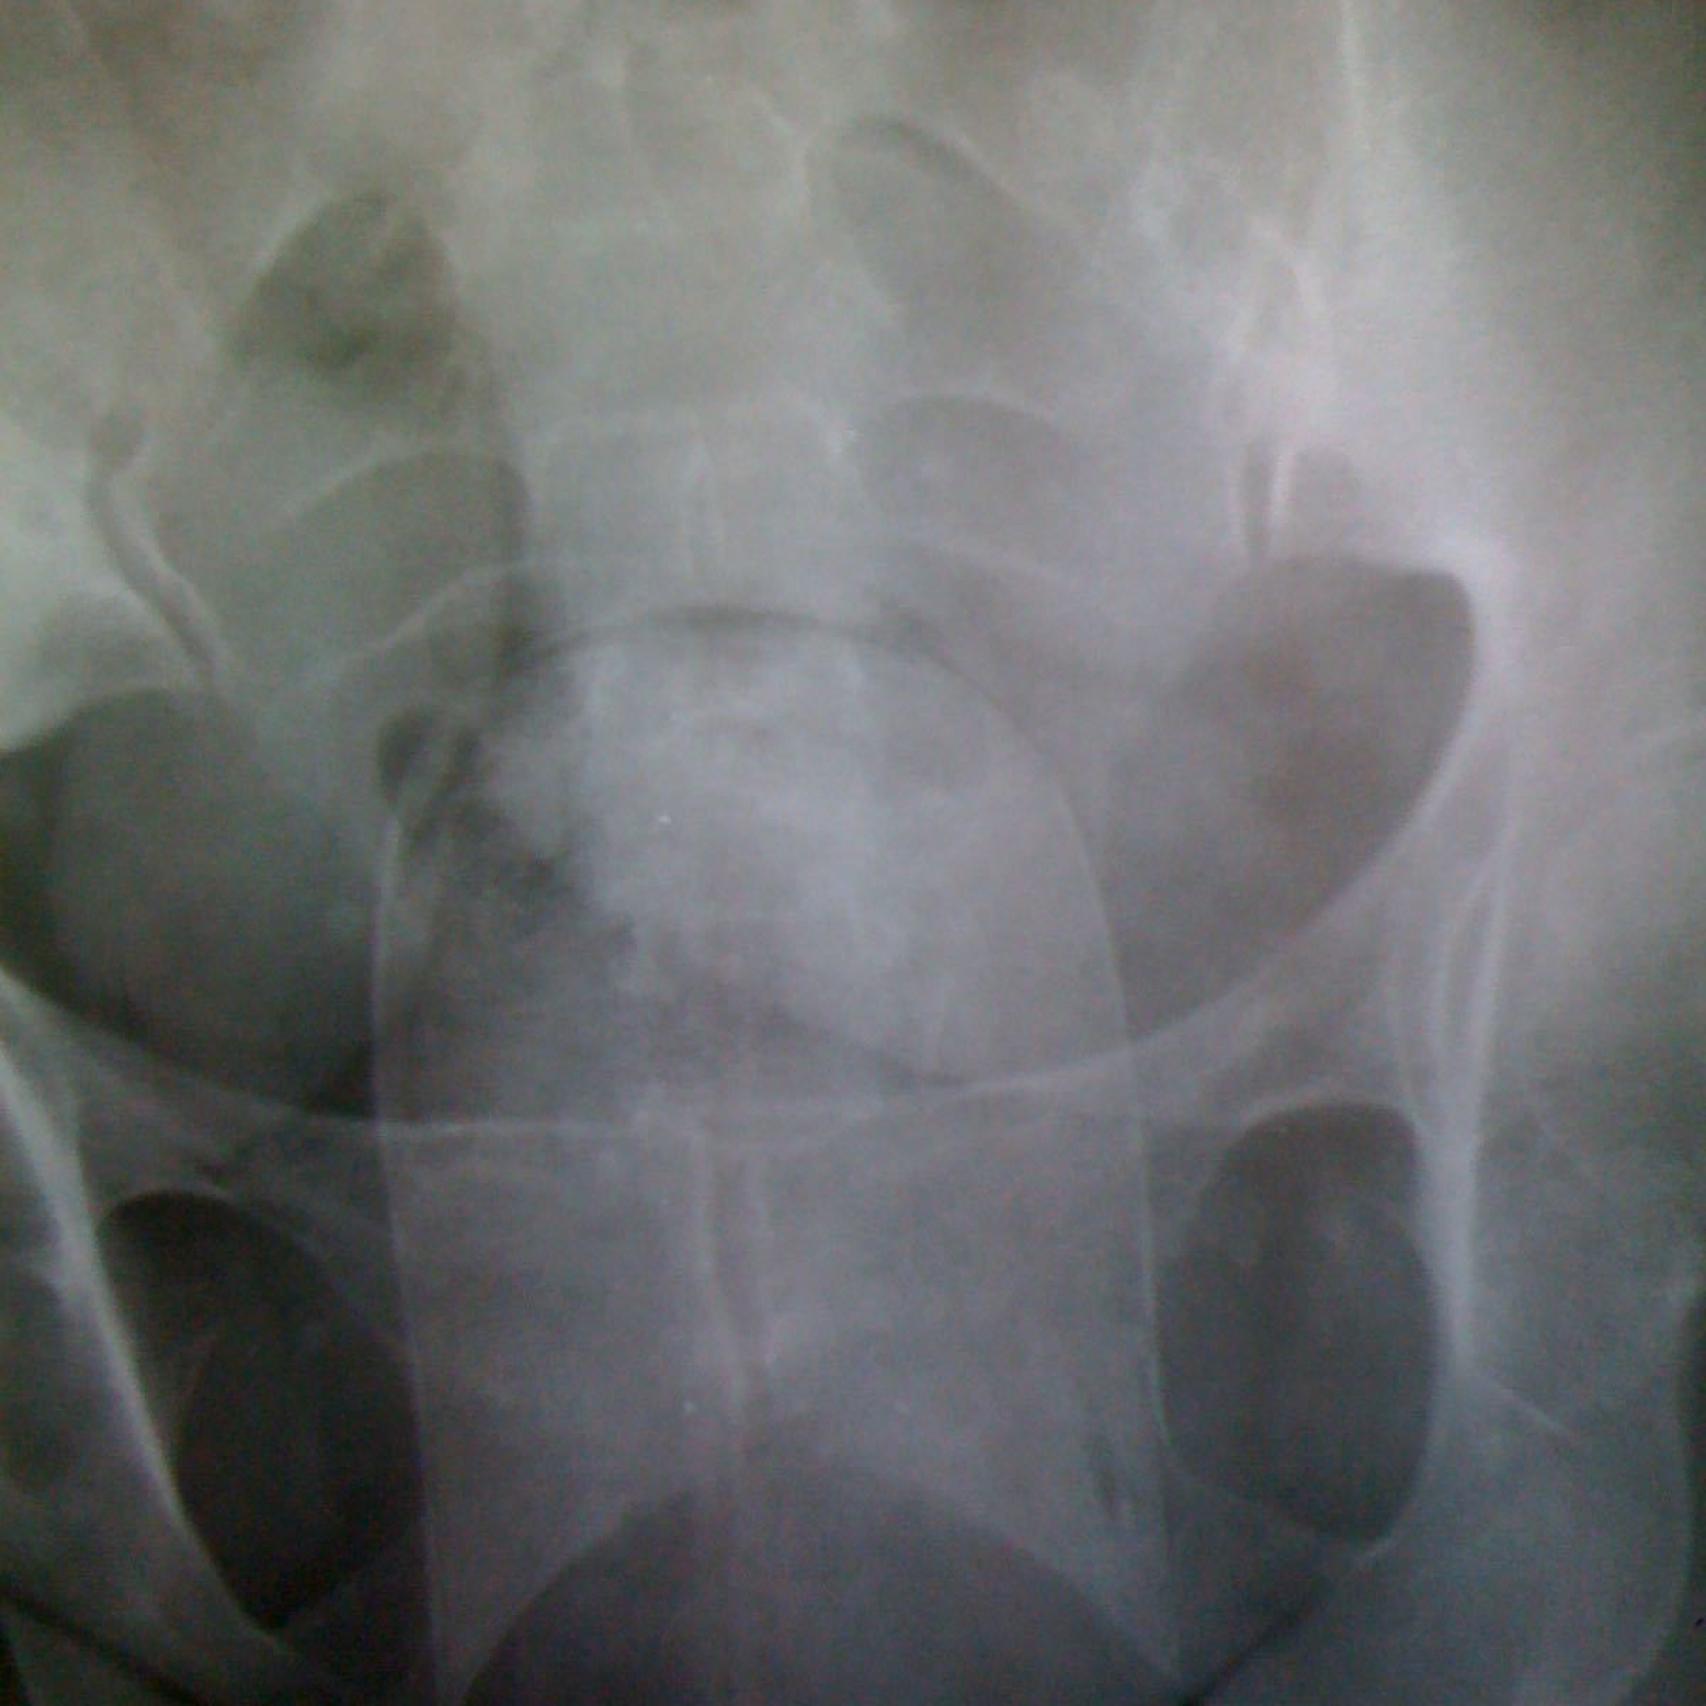

La radiografía revela la existencia de un 'pepino' de cocaína en el interior de la vagina

En la comisaría del aeropuerto de Barajas, once mujeres procedentes de Colombia son registradas por la Policía Nacional. Han llegado en un vuelo de Avianca y en dos de Iberia, procedentes todos del aeropuerto José María Córdova (Medellín). Los agentes sospechan que esconden droga. Tras negar los cargos, son examinadas en una sala de rayos X. Las radiografías revelan la presencia de cuerpos extraños en sus respectivos úteros. La más joven de todas, una chica de 22 años, pide entrar en los servicios y ahí se extrae un 'pepino' de la vagina. O lo que es lo mismo: un paquete de cocaína de casi 600 gramos de peso. Las dimensiones del bulto son tan grandes que la mujer acaba sangrando.